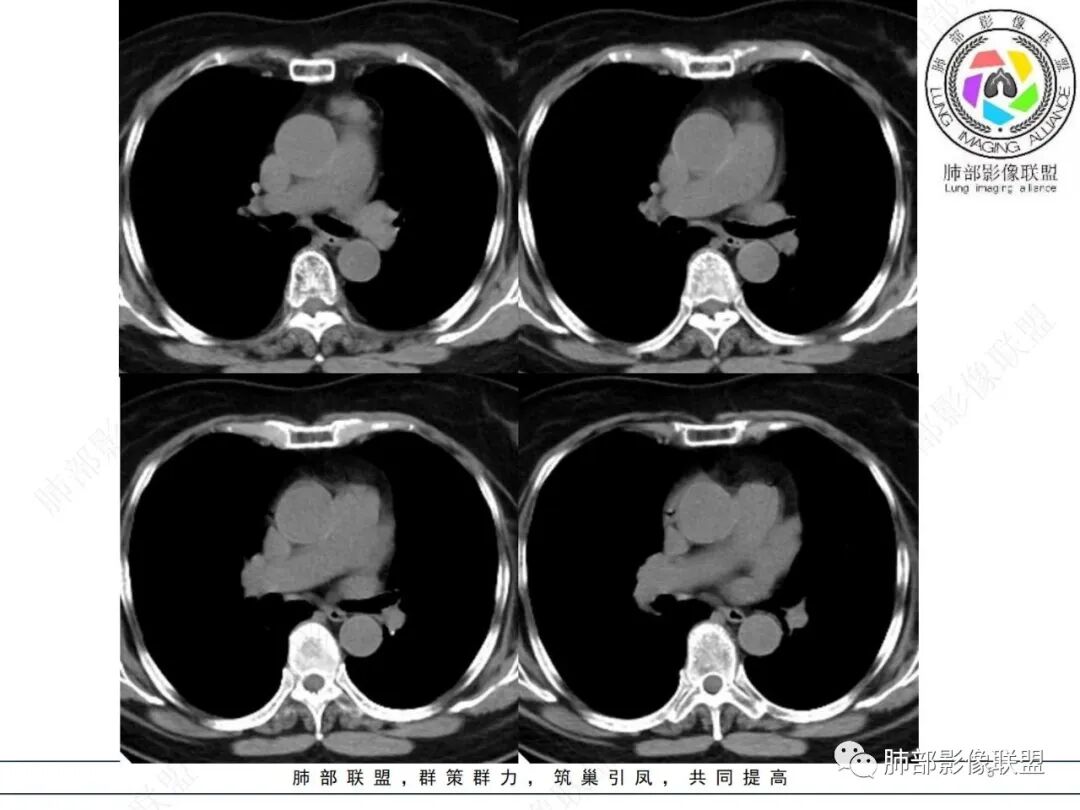

病史,老年女性,检查发现前上纵隔占位。

前上纵隔偏左侧实性病灶,边界清楚,边缘彭隆,浅分叶,内部密度均匀,未见钙化、脂肪密度,周围脂肪间隙清晰。

包膜完整,纤维分隔,结节感明显

平扫密度较均匀,增强渐进性不均匀强化,内见低密度纤维分隔。未见肿大淋巴结。未见胸腔积液。

肿块边界清楚,低密度纤维间隔,未见侵犯转移及增大淋巴结,多见于胸腺瘤AB型